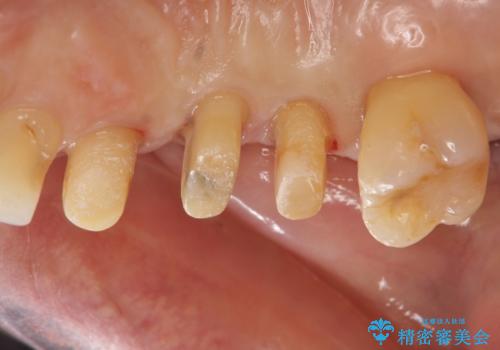

部分矯正を含む 歯周病治療 (再生治療・歯周ポケット除去・MTM・連結補綴)

- 歯のぐらつき、歯周病の検査を希望され来院されました。

検査の結果、強い歯ぎしりによる歯の周囲の骨の吸収が認められたため歯槽骨の再生・歯周ポケットの除去・力に対抗する連結補綴・補綴前処置としての小矯正を計画します。

今回連結補綴を行うにあたり、歯周病の問題を解決するために再生療法・歯周ポケット除去手術を、またより歯の神経を保存し力に対抗できる環境を整えるために小矯正を行い精度の高いメタルボンドクラウンを製作することができました。